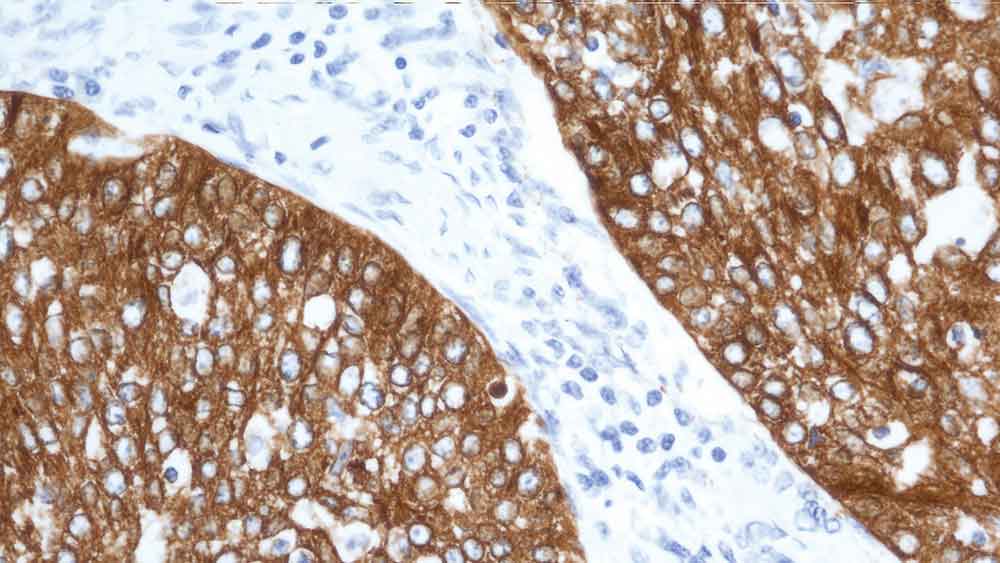

Human rectal adenocarcinoma: immunohistochemical staining for Cytokeratin 19. Note: cytoplasmic staining of malignant epithelial cells. Cytokeratin 19: clone b170

A proteína de filamento de citoqueratina humana menor (40 kD), foi identificada como citoqueratina 19 e foi reportada como expressa em um grande número de tipos de células epiteliais, incluindo muitos epitélios ductais e glandulares.

NCL-CK19 produz um padrão de coloração heterogênea complexa em epitélio escamoso não-queratinizado e folículos pilosos, com forte coloração da camada basal observada.